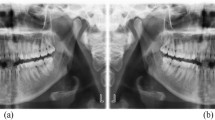

Altogether, 412 patients with maxillary cyst-like lesions (including several benign tumors) were enrolled. All panoramic radiographs were arbitrarily assigned to the training, testing 1, and testing 2 datasets of the study. The deep learning process of the training images and labels was performed for 1000 epochs using the DetectNet neural network. The testing 1 and testing 2 images were applied to the created learning model, and the detection performance was evaluated. For lesions that could be detected, the classification performance (sensitivity) for identifying radicular cysts or other lesions were examined.

The recall, precision, and F-1 score for detecting maxillary cysts were 74.6%/77.1%, 89.8%/90.0%, and 81.5%/83.1% for the testing 1/testing 2 datasets, respectively. The recall was higher in the anterior regions and for radicular cysts. The sensitivity was higher for identifying radicular cysts than for other lesions.

Using deep learning object detection technology, maxillary cyst-like lesions could be detected in approximately 75–77%.